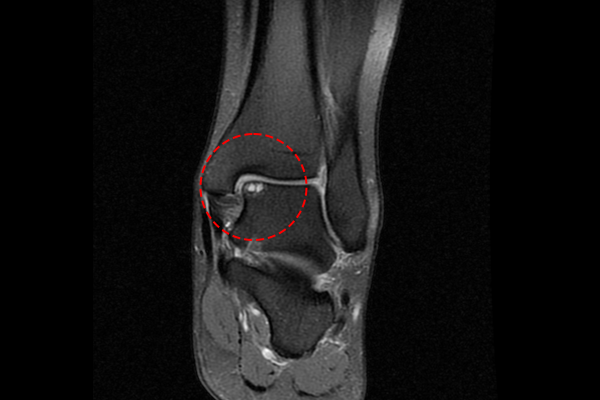

환자분의 발목 상태를 자세히 파악하기 위해서 MRI 촬영을 진행하였고,

MRI에서 발목 거골 부위 연골 손상과 골 괴사가 확인되었기에 발목 거골 골연골병변(박리성, 이단성 골연골염, 연골손상)(t. ankle osteochondral lesion of talus)을 진단하였습니다.